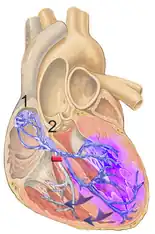

| An illustration of a right bundle branch block located in intraventricular septum | |

A right bundle branch block (RBBB) is a heart block in the right bundle branch of the electrical conduction system.[1]

During a right bundle branch block, the right ventricle is not directly activated by impulses travelling through the right bundle branch. The left ventricle, however, is still normally activated by the left bundle branch. These impulses are then able to travel through the myocardium of the left ventricle to the right ventricle and depolarize the right ventricle this way. As conduction through the myocardium is slower than conduction through the bundle of His-Purkinje fibres, the QRS complex is seen to be widened. The QRS complex often shows an extra deflection that reflects the rapid depolarisation of the left ventricle followed by the slower depolarisation of the right ventricle.